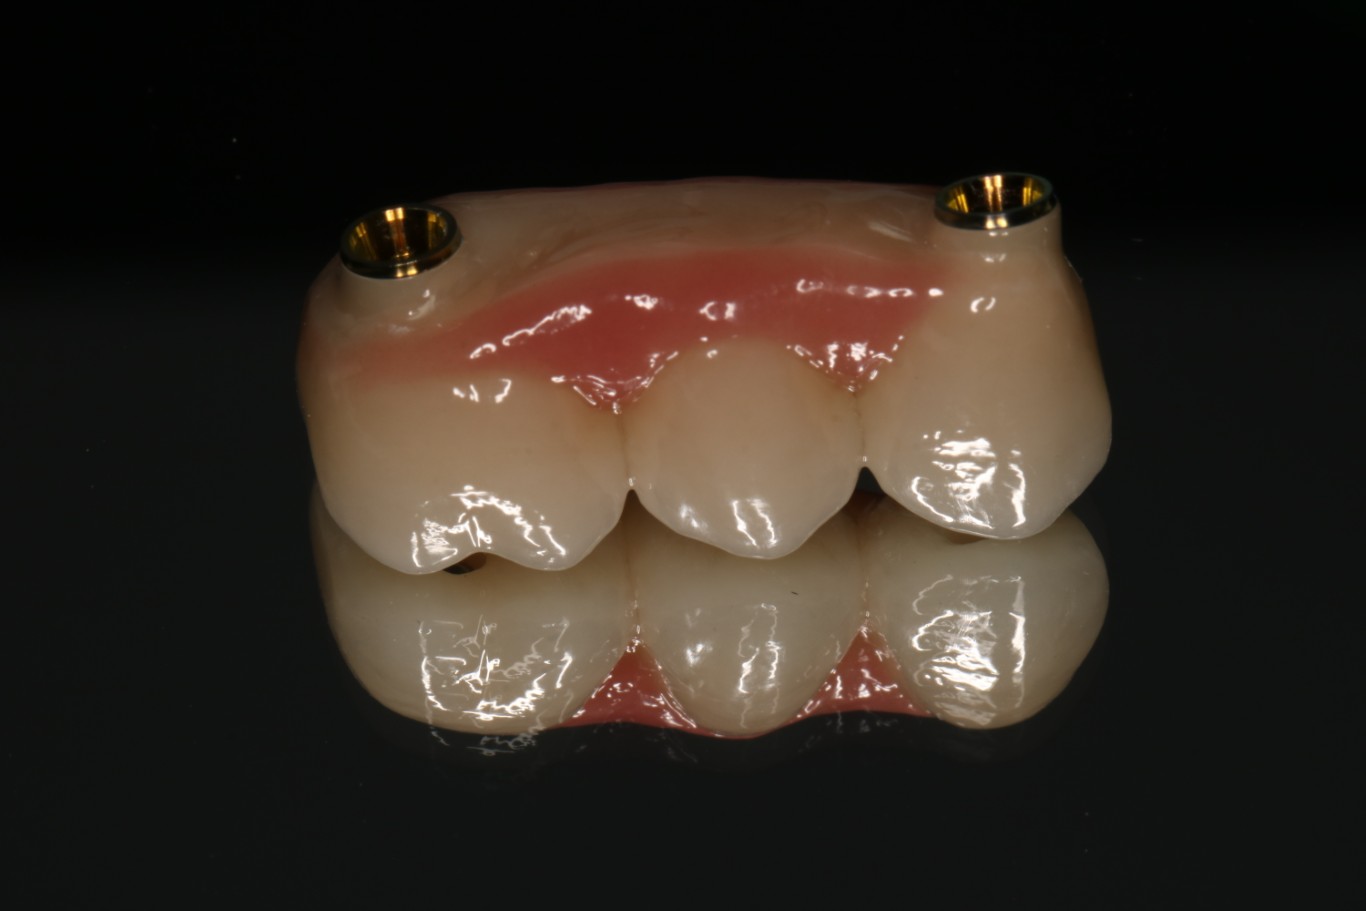

3. Protezy na koronach teleskopowych – elegancja i precyzja

Korony teleskopowe to najbardziej zaawansowane technicznie rozwiązanie w protetyce ruchomej na implantach. System działa na zasadzie “korona w koronie” – na implanty osadzone są stałe korony (korony pierwotne), a na nie nakładana jest proteza z koronami wtórnymi, które idealnie do nich przylegają.

Zasada działania:

Na każdy implant zakręcana jest precyzyjnie wykonana korona pierwotna. Proteza posiada wewnątrz odpowiadające im korony wtórne. Połączenie typu teleskopowego zapewnia doskonałe dopasowanie i retencję mechaniczną – proteza “wsuwana” jest pionowym ruchem i trzyma się niezwykle stabilnie bez dodatkowych zapięć.